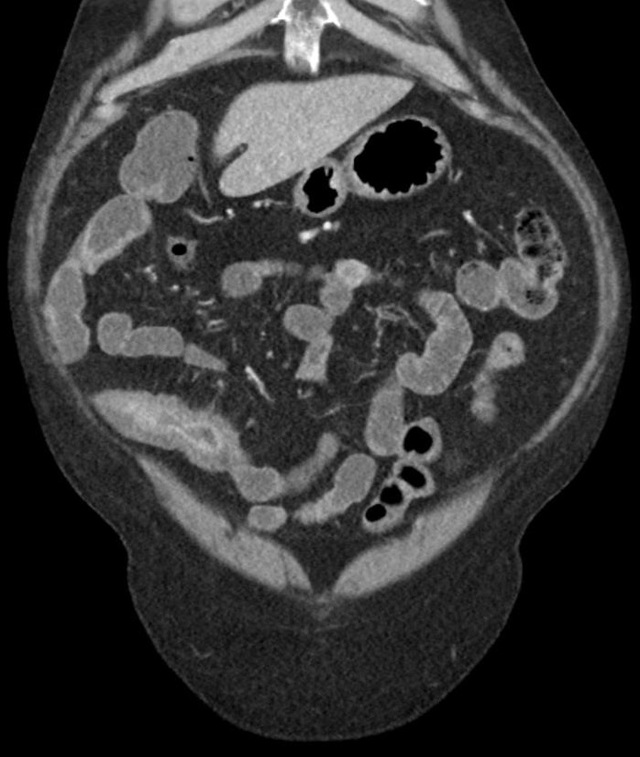

克罗恩病,这个名字听起来就像是来自某个遥远星球的神秘疾病,但实际上,它就在我们身边,悄无声息地侵蚀着无数人的健康。对我来说,克罗恩病不仅仅是一个医学名词,它更像是一颗定时炸弹,随时可能在我们最不经意的时候引爆。

想象一下,你正享受着美食,突然间肚子开始剧痛,那种痛,就像是被无数小刀在肚子里乱砍。你以为只是简单的消化不良,但其实是克罗恩病在作祟。这种病,让人无法预测,无法控制,它可以在任何时候,任何地点,给你致命一击。

更糟糕的是,克罗恩病不仅仅影响你的身体,它还深深地影响你的心理。每一次的疼痛,每一次的复发,都在无形中增加你的恐惧和焦虑。你开始害怕社交,害怕外出,甚至害怕进食。生活,就这样被克罗恩病一点点蚕食。

但你知道吗?克罗恩病并不是绝症,虽然它无法根治,但通过合理的治疗和管理,很多患者依然可以拥有相对。